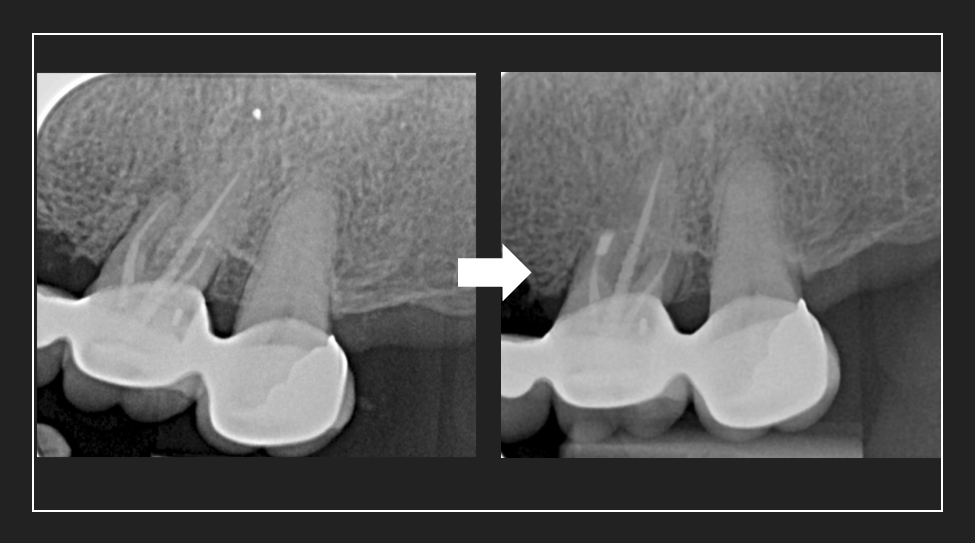

Root canal retreatment by Dr. Jonathan Sin